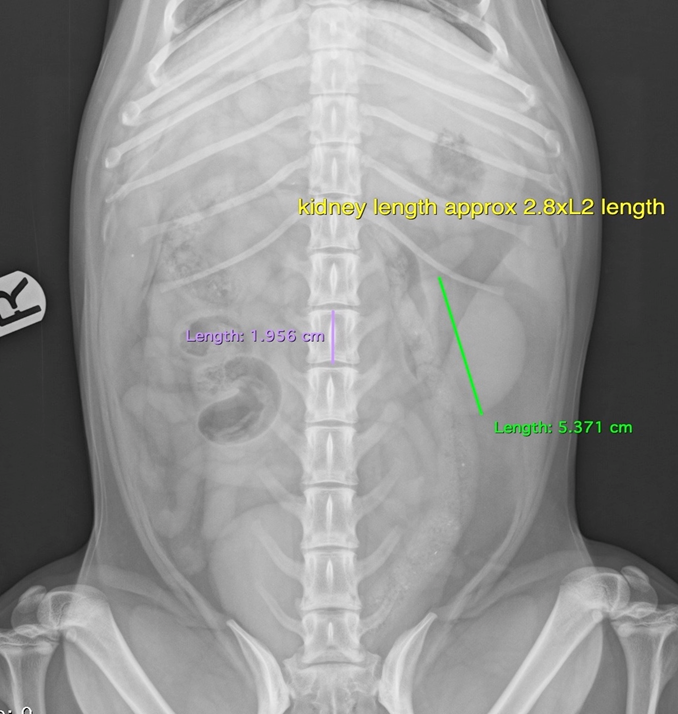

Describe the features of the kidney in survey radiography

Retroperitoneal

R more cranially (cranial pole T13)

L L1-L3

Length

Dogs —> 2.5-3.5 x L2 length

Cats —> 2.4-3 x L2 length

What is being shown in this radiograph and what are the possible causes?

Enlarged kidney —> increased soft tissue opacity in kidney

DDX = Cysts, haemorrage, abscess, neoplasia, granulomatous inflam, hydronephrosis

Metastasis of neoplasia (smaller circles)